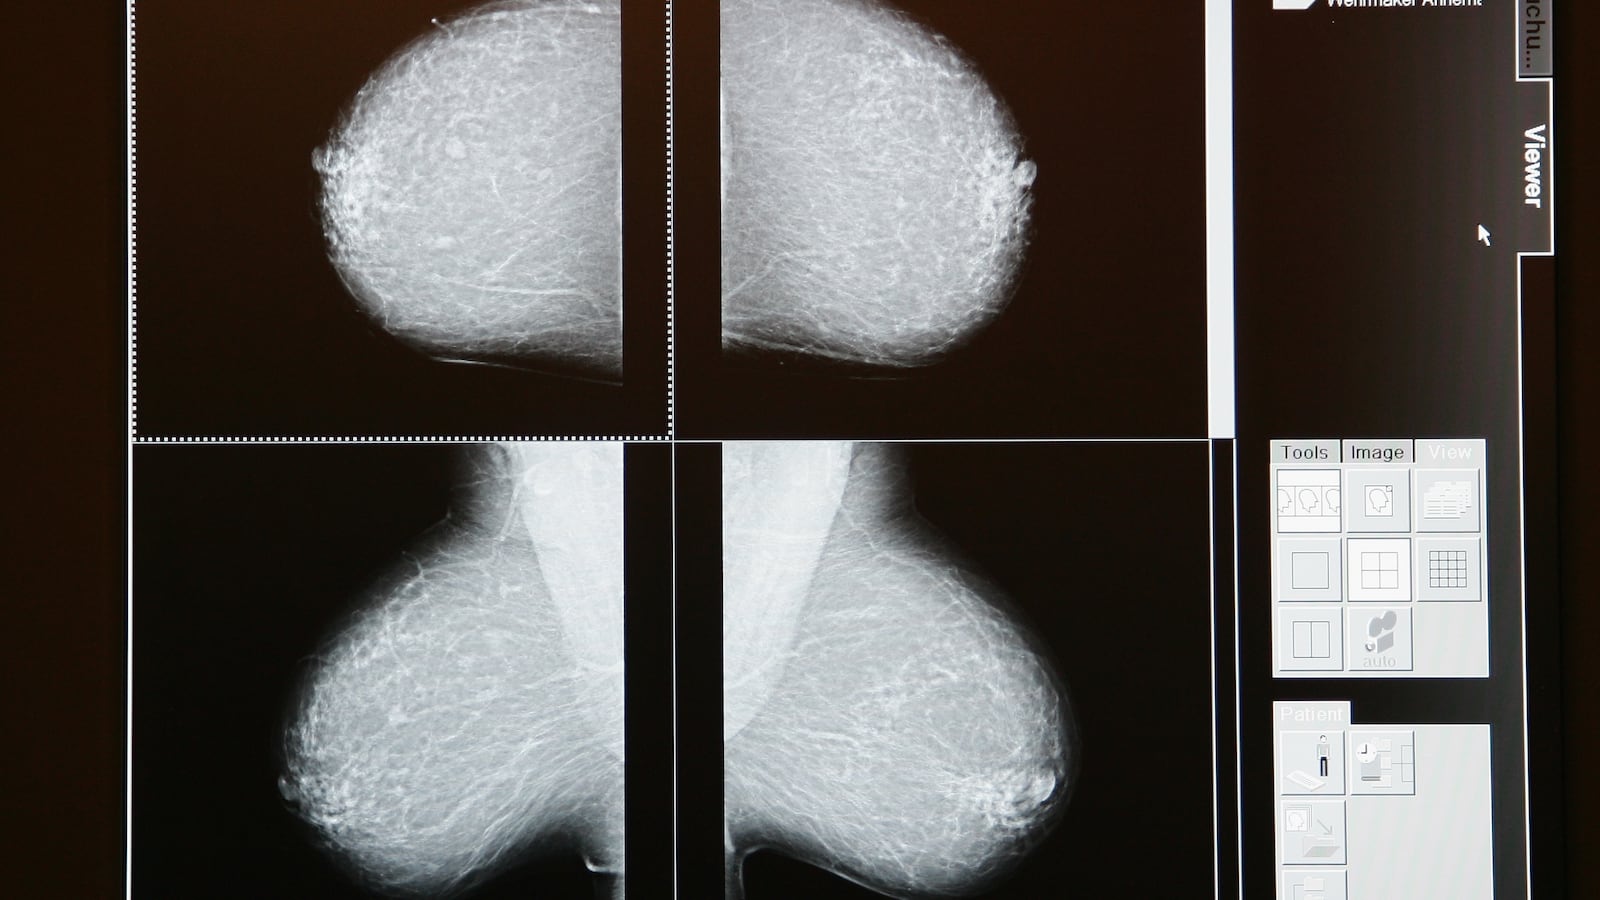

A computer algorithm was able to diagnose breast cancer more accurately than a radiologist—and just as well as two doctors examining a mammogram. That’s according to a new study published Wednesday in the journal Nature. Researchers from Google and Imperial College London teamed up to teach a computer model how to recognize cancer by feeding it the scans of 29,000 women. Then they put it to the test. According to the BBC, artificial intelligence had 1.2 percent fewer false positives and 2.7 percent fewer false negatives than the humans—who also had patient health histories to help them.

Read it at BBC